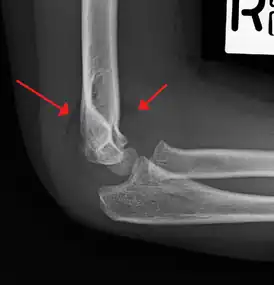

Fat pad sign/sail sign - A non-displaced fracture can be difficult to identify and a fracture line may not be visible on the X-rays. However, the presence of a joint effusion is helpful in identifying a non-displaced fracture. Bleeding from the fracture expands the joint capsule and is visualized on the lateral view as a darker area anteriorly and posteriorly, and is known as the sail sign.[8]

Anterior and posterior sail sign in a child who has a subtle supracondylar fracture